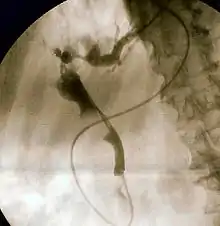

Endoscopic retrograde cholangiopancreatography (ERCP) is a technique that combines the use of endoscopy and fluoroscopy to diagnose and treat certain problems of the biliary or pancreatic ductal systems. It is primarily performed by highly skilled and specialty trained gastroenterologists. Through the endoscope, the physician can see the inside of the stomach and duodenum, and inject a contrast medium into the ducts in the biliary tree and pancreas so they can be seen on radiographs.

The patient is sedated or anaesthetized. Then a flexible camera (endoscope) is inserted through the mouth, down the esophagus, into the stomach, through the pylorus into the duodenum where the ampulla of Vater (the union of the common bile duct and pancreatic duct) exists. The sphincter of Oddi is a muscular valve that controls the opening to the ampulla. The region can be directly visualized with the endoscopic camera while various procedures are performed. A plastic catheter or cannula is inserted through the ampulla, and radiocontrast is injected into the bile ducts and/or pancreatic duct. Fluoroscopy is used to look for blockages, or other lesions such as stones.[8][9]

When needed, the sphincters of the ampulla and bile ducts can be enlarged by a cut (sphincterotomy) with an electrified wire called a sphincterotome for access into either so that gallstones may be removed or other therapy performed.[10]

Other procedures associated with ERCP include the trawling of the common bile duct with a basket or balloon to remove gallstones and the insertion of a plastic stent to assist the drainage of bile.[11] Also, the pancreatic duct can be cannulated and stents be inserted.